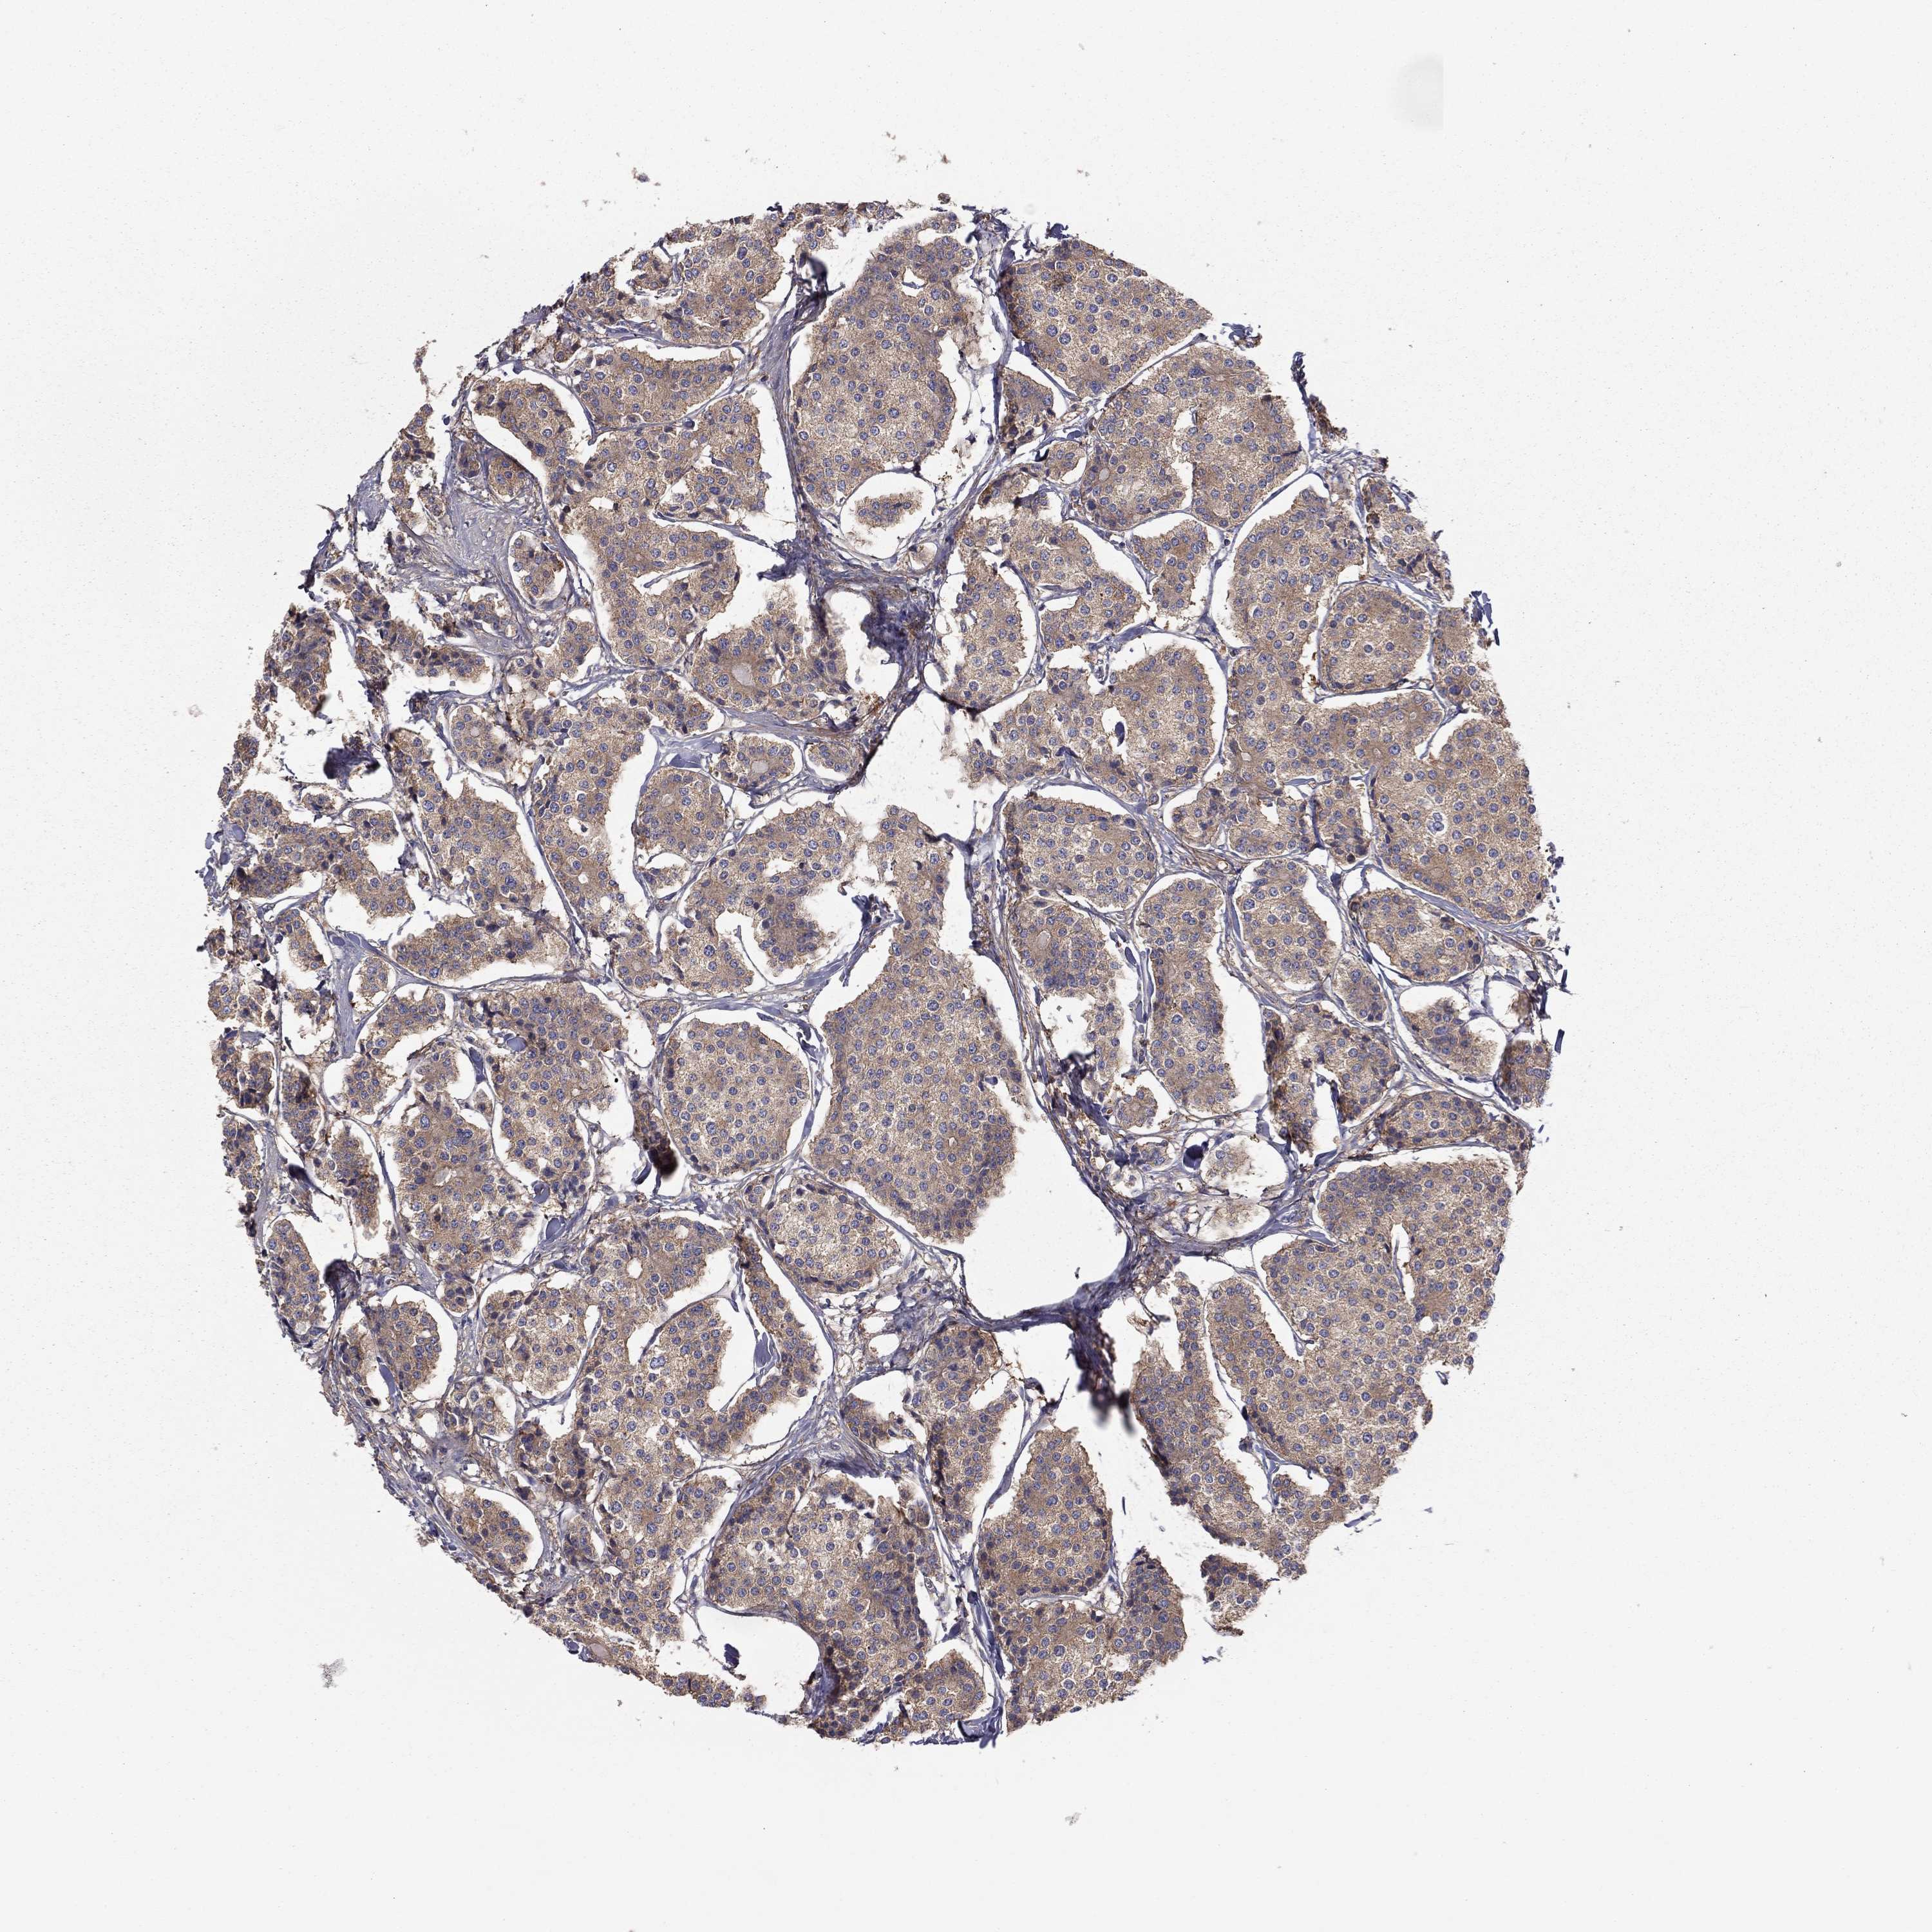

CARCINOID - Protein expressioni

A mouse-over function shows sample information and annotation data. Click on an image to view it in a full screen mode. Samples can be filtered based on level of antibody staining by selecting one or several of the following categories: high, medium, low and not detected. The assay and annotation is described here.

Antibody stainingi

Antibody staining in the annotated cell types in the current human tissue is reported as not detected, low, medium, or high, based on conventional immunohistochemistry profiling in selected tissues. This score is based on the combination of the staining intensity and fraction of stained cells.

Each image is clickable and will lead to virtual microscopy that enables deeper exploration of all samples and also displays staining intensity scores, fraction scores and subcellular localization as well as patient and tissue information for each sample.

Antibody HPA065983

Antibody HPA071879

Carcinoid, malignant, NOS